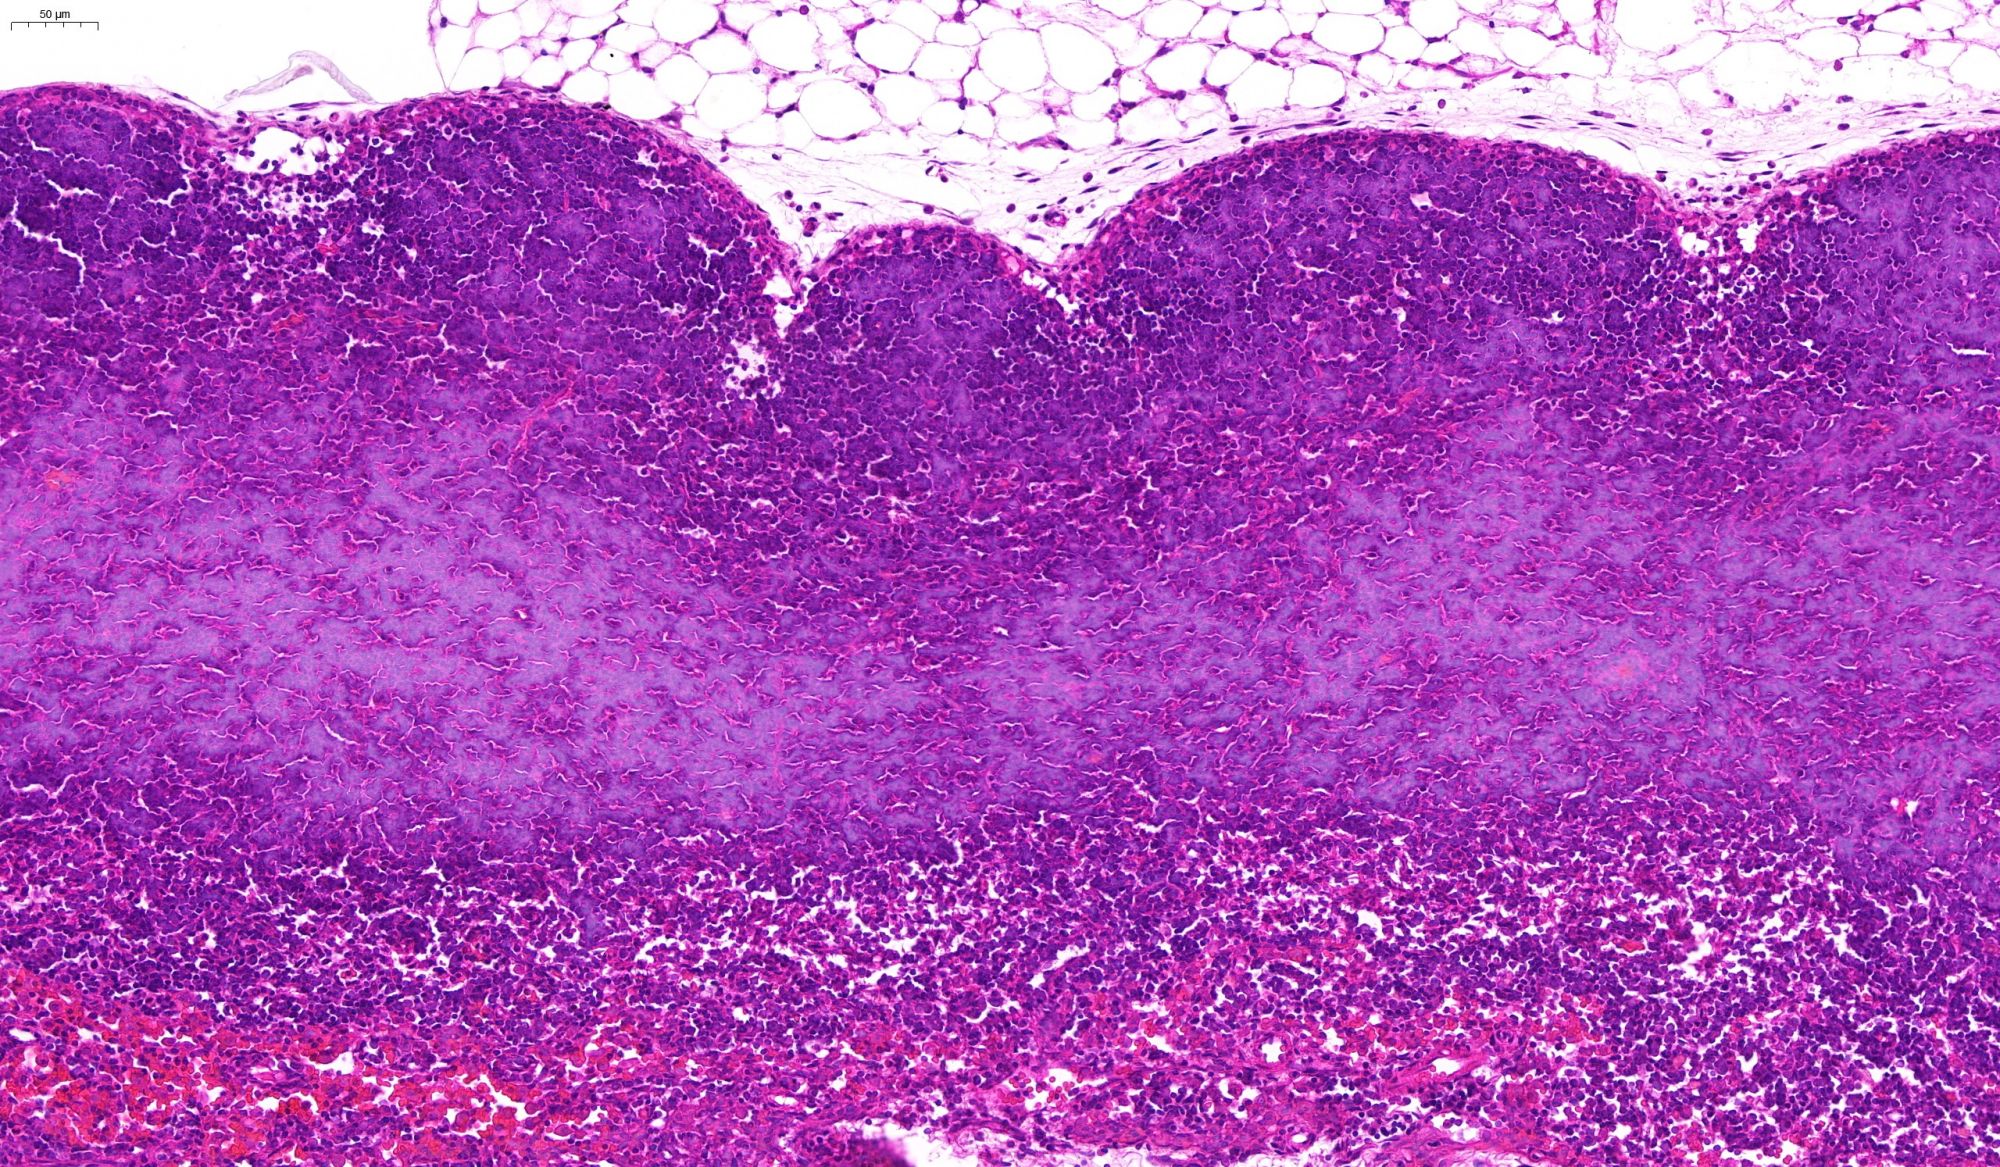

胰腺組織HE染色

HE染色

381